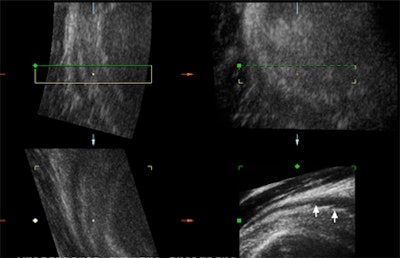

![]() |

| Above and below, post-traumatic multiplanar and enlarged 3D reconstruction of the supraspinatus tendon with small marginal tears that were better depicted using 3D reconstruction. |